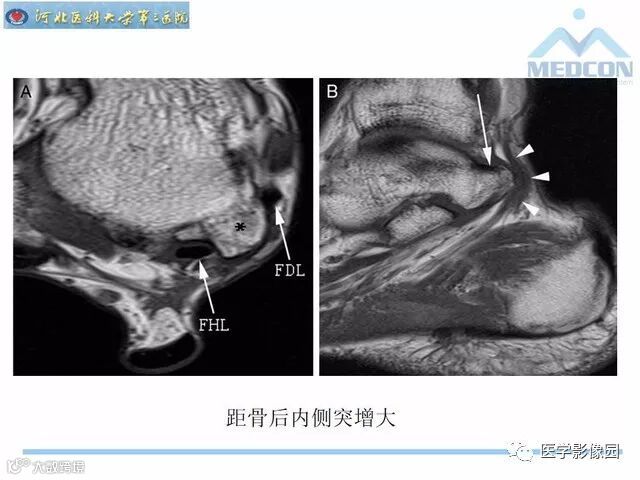

踝关节撞击综合征影像诊断,干货满满,值得收藏!

导读:踝关节撞击综合征影像诊断。干货满满,值得收藏!

踝关节撞击综合征影像诊断。干货满满,值得收藏!